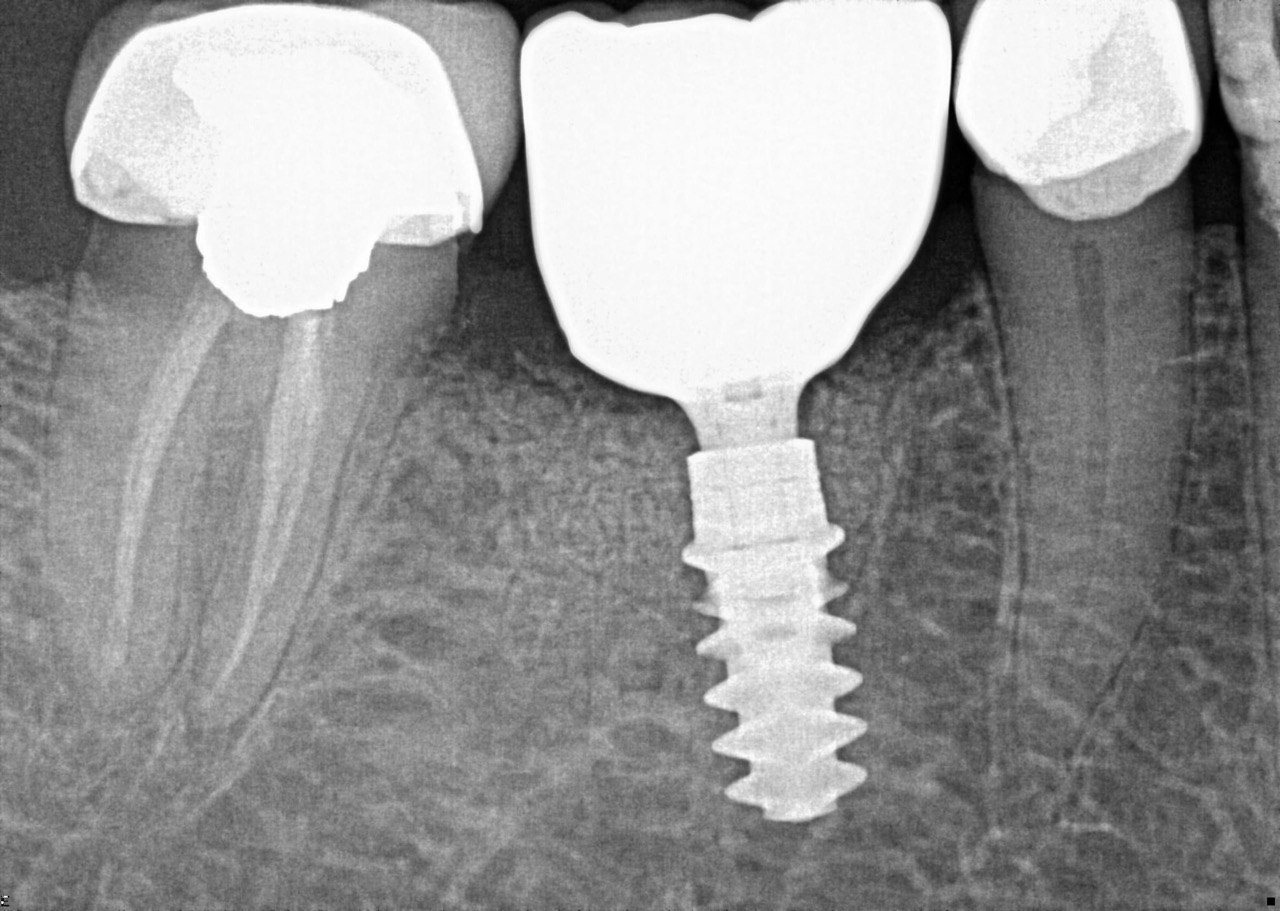

4. What option can be selected regarding the implant seen in this X ray?